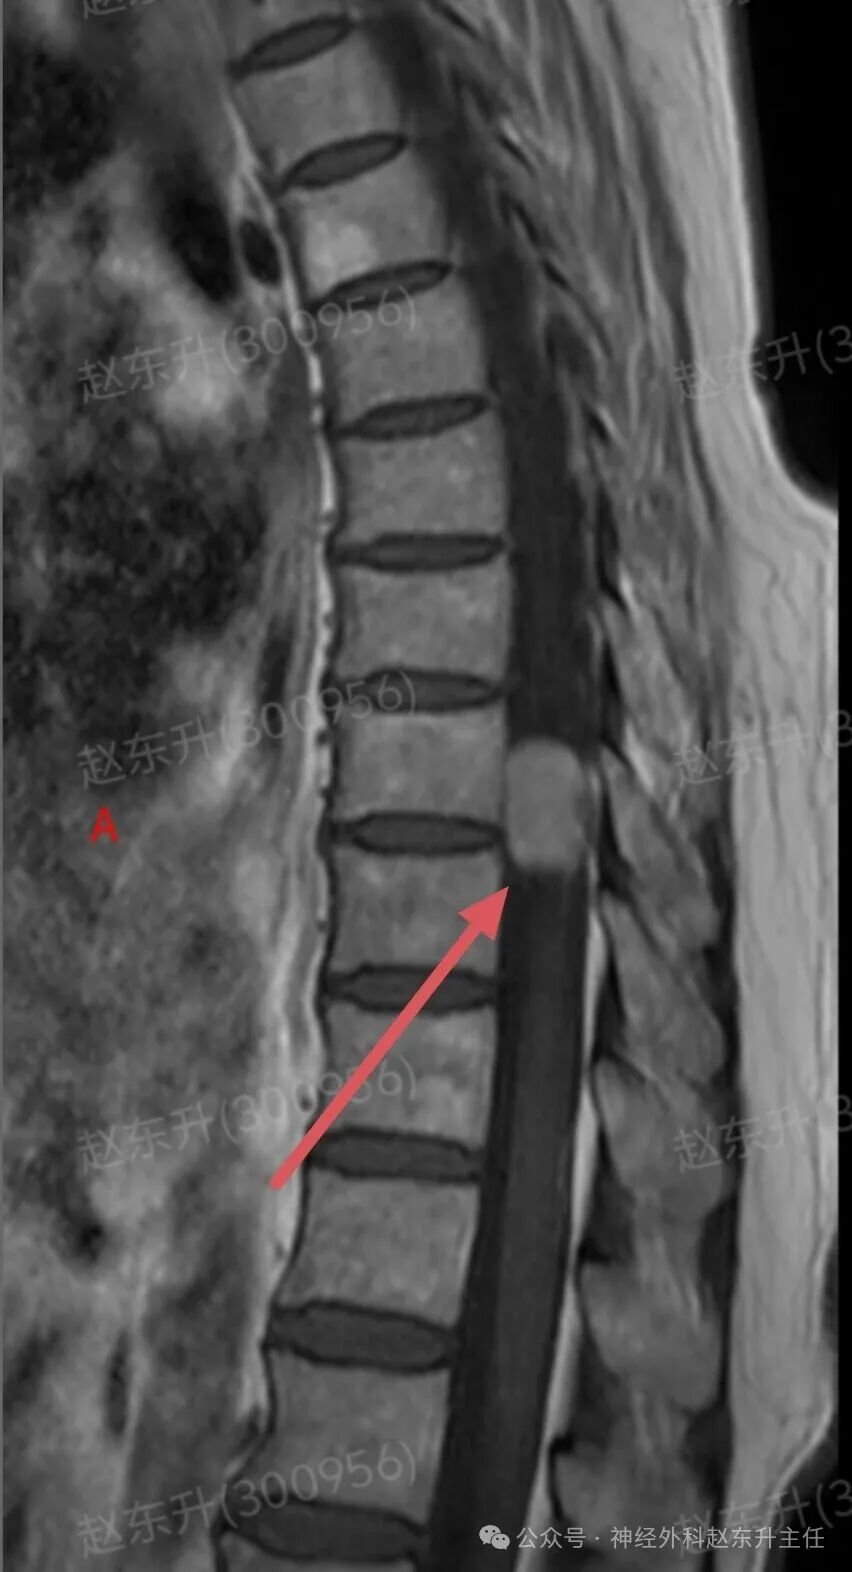

有一天门诊来了一位69岁的甘肃女性患者。因为长期腰腿疼,在多家医院就诊治疗无效,长期按摩针灸拔罐艾灸电疗磁疗腰腿疼,稍有缓解。随后又持续加重,在外院查腰椎磁共振,未见明显异常,随后在向上查胸椎磁共振,发现椎管内一个巨大肿瘤压迫脊髓比较明显。她疼痛评分有6分,夜间疼痛难忍,难以入睡。此次发现椎管肿瘤以后来到我院就医。根据胸椎磁共振的表现,考虑脊膜瘤可能。随后在全麻下,我们在显微镜下彻底切除了肿瘤组织术后患者疼痛缓解下地行走,较术前改善大小便也恢复正常了。

图片图片图片图片图片图片肌电图提示下肢神经、骶神经损伤术中切除的肿瘤组织西安市红会医院神经外科赵东升主任介绍:椎管内脊膜瘤是一种常见的、通常为良性的椎管内肿瘤,起源于覆盖脊髓和神经根的脊膜(特别是蛛网膜的“帽细胞”)。核心特征:性质:绝大多数(90%以上)为良性(WHO I级),生长缓慢。位置:可发生于椎管的任何节段,但最常见于胸椎(约占70%),其次是颈椎、腰椎少见。特点:肿瘤通常有完整的包膜,与硬脊膜基底紧密相连,像一颗“附着在墙壁上的珍珠”,可压迫脊髓和神经根,但通常不侵入神经组织本身。发病率:是椎管内最常见的肿瘤之一,约占所有椎管肿瘤的25%。好发于中年女性(女:男比例约为4:1),可能与激素水平有关。

病史与神经系统查体:医生通过询问病史和详细的神经系统检查,初步判断病变的节段和严重程度。影像学检查(确诊的关键):增强磁共振(MRI): 是诊断的金标准。典型表现:T1加权像上呈等或稍低信号,T2加权像上呈等或稍高信号;增强扫描后呈现显著的、均匀的强化。特征性的“硬脊膜尾征”(肿瘤附着处硬脊膜线状强化)具有重要诊断价值。可清晰显示肿瘤与脊髓、神经根的关系。CT扫描:可显示肿瘤是否伴有钙化(沙粒体型脊膜瘤常见),以及是否有椎体或椎弓根的骨质增生,但对软组织分辨率不如MRI。X线平片:作用有限,可能仅见椎弓根间距增宽等间接征象。